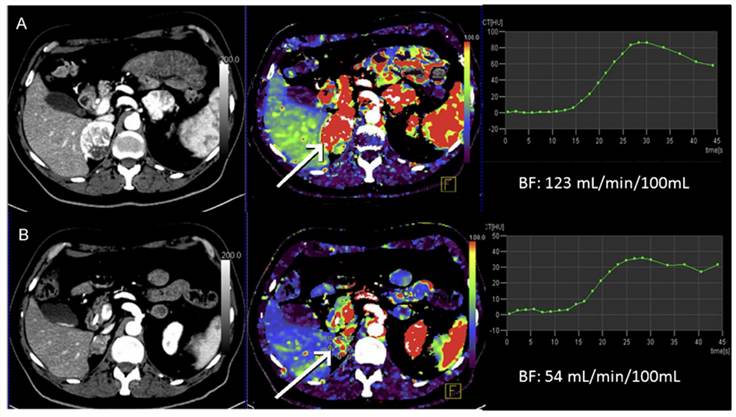

Conventional CT images and DCE-CT-derived regional blood flow maps. Fig.1 Conventional CT images and DCE-CT-derived regional blood flow maps.1

In addition, We can use DCE-CT to predict the response of a range of tumors, such as cervical, rectal, and lung cancers, to chemotherapy and provide accurate risk stratification. In a recent study, we found a strong correlation between reduced DCE-CT parameters and prolonged survival, which suggests that our data may serve as a proxy for later clinical trials.